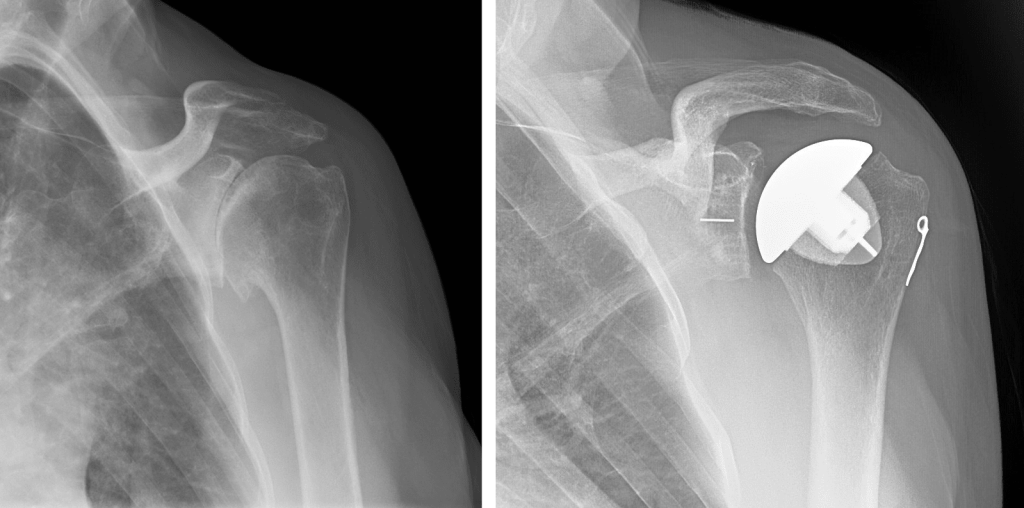

Shoulder Replacement

Shoulder replacement is a surgical procedure designed to relieve pain and restore function in severely damaged shoulder joints, typically due to arthritis, fractures, or degenerative joint diseases. During the procedure,...